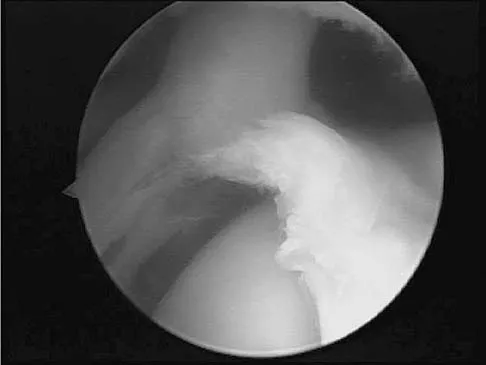

Which of the following anatomic structures is often difficult to visualize during elbow arthroscopy?

Explanation

The ulnar collateral ligament is often difficult to visualize during elbow arthroscopy. It can be seen clearly in only 10% to 30% of elbow arthroscopies. All of the other structures should be easily and thoroughly seen and palpated during elbow arthroscopy. Johnson LL: Arthroscopic Surgery: Principles and Practice. St Louis, MO, CV Mosby, 1988.